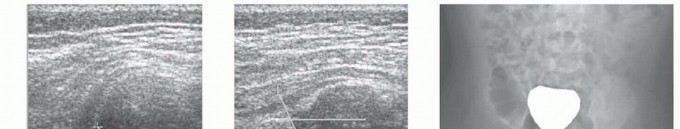

Anterior Drainage of the Septic Hip in Children DEFINITION Septic arthritis of the hip affects children of al…